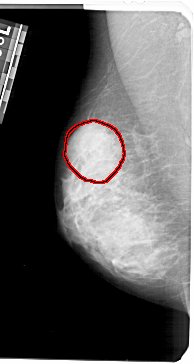

A_1353_1.LEFT_CC

LEFT_CC LINES 5191 PIXELS_PER_LINE 2581 BITS_PER_PIXEL 12 RESOLUTION 43.5 OVERLAY

FILE: A_1353_1.LEFT_CC.OVERLAY

TOTAL_ABNORMALITIES 1

ABNORMALITY 1

LESION_TYPE CALCIFICATION TYPE PLEOMORPHIC DISTRIBUTION SEGMENTAL

ASSESSMENT 4

SUBTLETY 2

PATHOLOGY BENIGN

TOTAL_OUTLINES 1

BOUNDARY